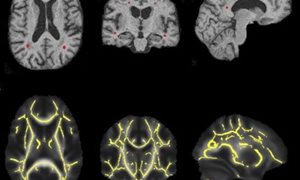

Cerebral Small Vessel Disease (SVD) is een verzamelnaam voor problemen in de kleine bloedvaten in de hersenen. Hierdoor ontstaan bijvoorbeeld hele kleine bloedingen of herseninfarcten. De slechtere doorbloeding beschadigt hersenweefsel en vermindert de functie van de hersenen. Hierdoor ontstaat een risico op dementie. Arts-onderzoeker Inge van Uden wilde weten welke patiënten met SVD een hoger risico hebben en volgde ruim 500 ouderen met SVD in de periode van 2006 tot 2015. Bij aanvang van de studie had geen van de deelnemers dementie. Gedurende de onderzoeksperiode volgde zij met de MRI-scanner de gevolgen van SVD in het brein.

In de eerste vijf jaar van het onderzoek ontwikkelde een deel van de proefpersonen dementie. Het bleek dat de patiënten die bij aanvang van de studie een verkleinde hippocampus en minder witte hersenstof hadden 50 procent meer kans hadden om in die periode dement te worden. Bij patiënten van wie de hippocampus nog goed van formaat was, maar waarvan de kwaliteit van de verbindingen verlaagd was, was het risico op dementie zelfs twee tot drie keer hoger. De MRI geeft dus een beter beeld van het risico op dementie dan alleen de aanwezigheid van SVD.

Als mensen op latere leeftijd voor het eerst in hun leven depressieve klachten krijgen, is dat een vroeg signaal voor dementie. Inge van Uden zag dit effect ook terug in haar onderzoekspopulatie, onafhankelijk van de ernst van de SVD. Patiënten met depressieve klachten op hogere leeftijd hadden minder goede hersenverbindingen in de prefrontale cortex, het hersengebied dat een rol speelt in het reguleren van gedrag en stemming. Opvallend was dat dit effect het sterkst was bij mensen die cognitief goed functioneerden. Inge van Uden: “Misschien vormt een laag cognitief vermogen op zich al een sterk risico op dementie, waardoor het aanvullende effect van depressieve symptomen beperkt is.”